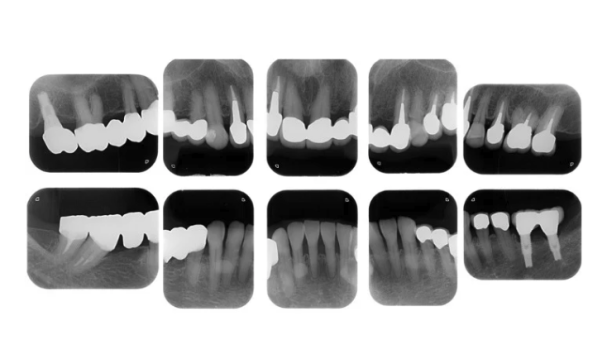

| 主訴 | 歯がグラグラで噛むことができない。インプラントをして欲しい。 |

| 治療内容 | 歯周病で骨の吸収が重度で保存不能なため抜歯、仮の入れ歯を作り、6ヶ月の抜歯窩の治療の後に、インプラントのCTによる診査診断を行い、下顎に6本インプラント埋入と同時に仮歯を入れる。その後、上顎は8本のインプラント埋入と同時に仮歯を入れる。左右上6はソケットリフトによる上顎洞拳上術を行う。その後免荷期間6ヶ月待ってセラミックを用いた上部構造作製、装着しメンテナンスに移行する。 |

| 治療費 | 9,000,000円(税込) |

| 治療期間 | 2年3ヶ月 |

| 治療回数 | 90回 |

| 想定されたリスク | 重度の歯周病により無歯顎になったため、プラークコントロール不良による、術後のインプラント周囲炎が懸念される。歯冠の部分はセラミックなため欠ける可能性がある。 |